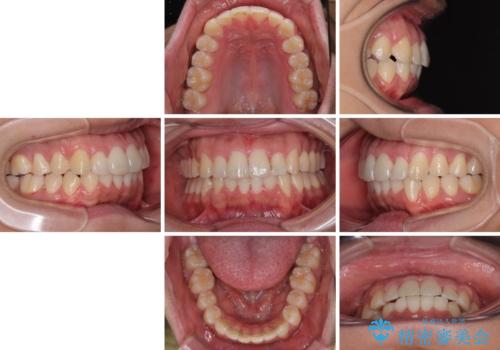

前方に捻れた前歯を治したい インビザライン矯正治療

- 前歯のデコボコを治したいとのことで来院された患者様です。

上下顎ともに歯列全体の後方移動とIPR(歯と歯の間を削る)によってデコボコが解消するように設計し、インビザラインにより治療を行うこととしました。

下顎前歯は後戻りを起こしやすいため、舌側を細いワイヤーで固定し、マウスピース型リテーナーで保定を行うこととしました。